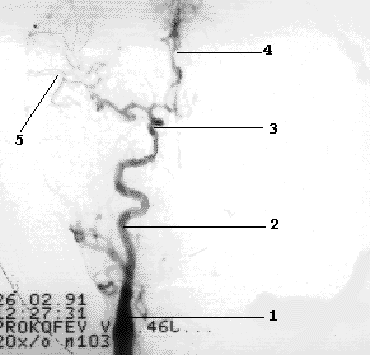

Наружная сонная артерия имеет короткий ствол, делясь на ряд ветвей, что легко позволяет отличить ее от ВСА. Насчитывают девять ветвей НСА, ряд из которых (терминальные ветви лицевой, поверхностной височной и верхнечелюстной артерий) анастомозируют с конечными ветвями глазничной артерии (первая интракраниальная ветвь ВСА) (Рис 1.4).

Рис 1.4.

Схема глазничного анастомоза.

1-

ОСА, 2- НСА, 3- лицевая артерия, 4- ПВА, 5-

ГА, 6-глазничный анастомоз.